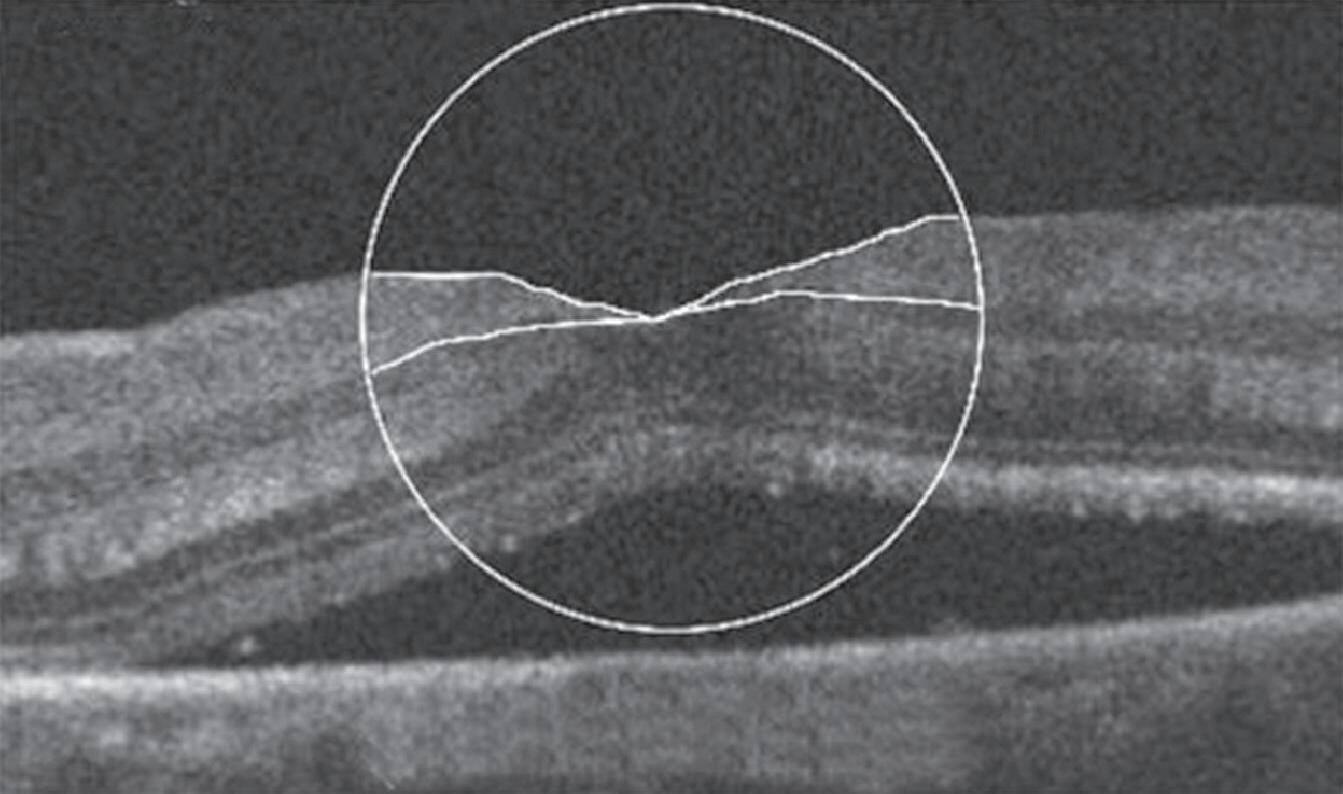

Um exemplo da capacidade da OCT para prever a acuidade visual pós-operatória em olhos com descolamento de retina regmatogênico (RRD) sem mácula está na Figura 1-27.20 Outras áreas da medicina se beneficiam igualmente da técnica da tomografia de coerências ótica . Para citar algumas: dermatologia no diagnóstico de lesões da pele como carcinomas etc. Na cardiologia se usa para obter imagens de alta resolução das artérias coronárias. O método de OCT por endoscopia foi introduzido em 1997 pelo pesquisador James Fujimoto no MIT e outros colaboradores. Finalmente, na indústria de semicondutores na medição não destrutiva das camadas finas dos seus dispositivos. O campo das aplicações do uso da OCT é cada vez mais amplo e se pode afirmar que novos e melhores equipamentos estão por vir.

1-27. Imagens pré-operatórias de tomografia de coerência óptica (oCT). Um círculo com um diâmetro de 2 mm foi posicionado manualmente no centro da superfície foveal da mácula destacada na imagem de oCT. a área macular dentro do círculo foi dividida em três seções: camada interna (superior direita: camada de fibras nervosas e camada de células ganglionares), camada intermediária (inferior direita: camada plexiforme interna e camada nuclear interna) e camada externa (inferior esquerda: camada plexiforme externa e camada nuclear externa). (reproduzida com permissão de https://www.hindawi.com/copyright/.)20